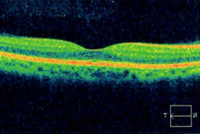

網膜断層検査(光干渉断層計 OCT)

近赤外線を利用して網膜の断面の状態を調べます。網膜のむくみや新生血管などが観察できます。

網膜の水ぶくれが中心にかかっていれば、水ぶくれの原因物質を中和するアバスチンという薬を注射したり、原因物質を拡散させるために硝子体手術を行ったりします。また、将来悪性の緑内障にならないように血管の詰まった部分をレーザーで焼きます。当院の光干渉断層計で、水ぶくれが中心にかかっているかどうかの判定が確実にできます。